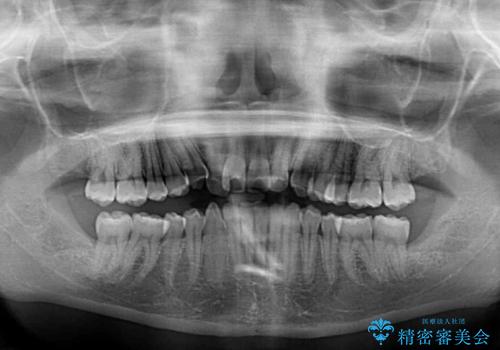

- 前歯のデコボコを気にして来院された患者様です。

上顎右側犬歯が八重歯になっており、それによって奥歯が前方に移動しているため、右側の咬み合わせの改善が必要と判断されました。

より治療を速やかに行うため、上顎右側にアンカースクリューを使用し、目標としていた1年半ほどで治療を終えることができました。